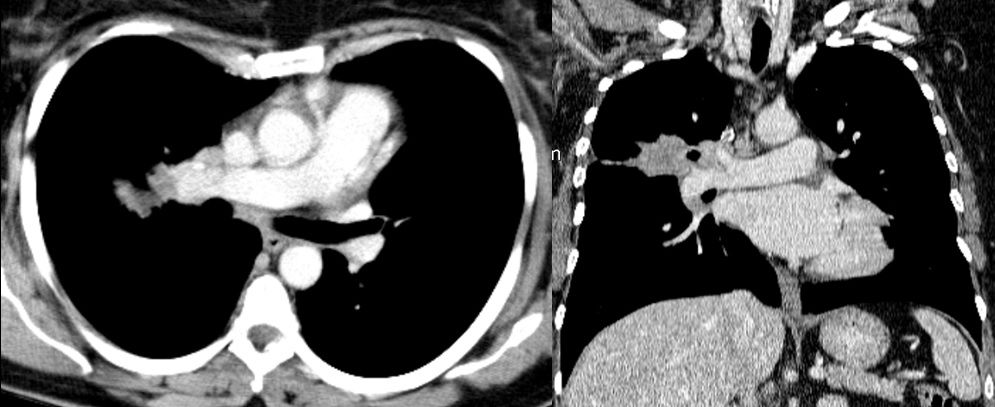

This video shows a 49-year-old woman with a 3.8 cm right upper lobe tumor, surrounding the segmental division of the upper lobe bronchus. The tumor was very close to the pulmonary artery (PA), and had extended contact with the minor fissure (Figure 1). There were also enlarged lymph nodes posterior to the anterior trunk of the PA surrounding the upper lobe bronchus and posterior to the middle lobe bronchus.